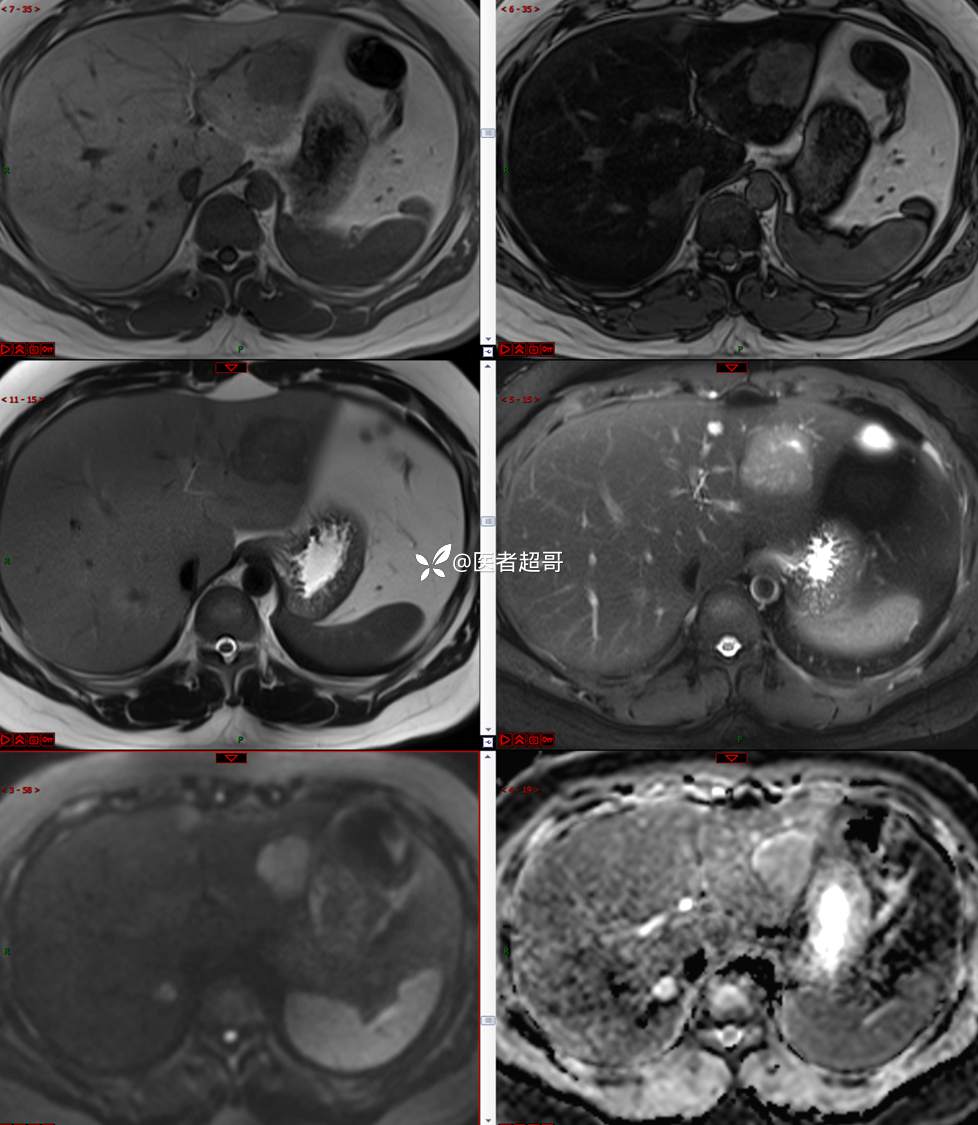

【影诊笔记685】男,31y,发现肝占位性病变5天就诊,请诊断分析,有病理结果!

主 诉:发现肝占位性病变5天。

现病史:患者缘于5天前体检时发现肝占位性病变,未予以特殊处置。现患者为求系统诊治就诊于我院,行普美显提示:肝左叶富血供占位,请结合临床及其他检查,肝多发血管瘤,脂肪肝,肝囊肿,请结合临床。门诊以“肝占位性病变”收入我科。病程中,饮食睡眠可,二便可,近期体重未见明显变化。